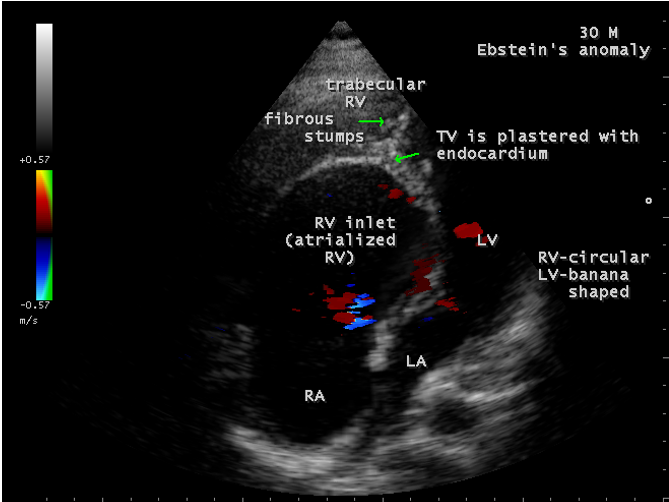

A 30-year old male was presented with marked cyanosis and no murmur and abnormal heart sounds on auscultation. 2D echocardiography revealed the features of Ebstein’s anomaly such as insertion of anterior leaflet into the trabeculated RV, forming a ‘blanket’ of leaflet tissue across the inflow and trabecular parts and bulging of ventricular septum towards leftward due to marked dilatation of RV, and LV became ‘banana’ shaped as shown in Figures 28 to 30.

The anterior tricuspid leaflet is not involved in the process of downward displacement, it may be abnormally inserted occasionally and Shiina, et al documented the apical displacement of anterior tricuspid leaflet in 14% of cases echocardiographically [39]. The anterior leaflet forms a large, sail-like intracavitary curtain as in Figures 14, 25 and contains muscular strands instead of consisting entirely of a fibrous membrane as in the normal tricuspid valve [40]. It is potentially mobile with a brisk sail-like movement as shown in Figure 21 to 24 [41], free bloating with a ‘whipping motion’ across the right ventricular outflow tract (RVOT) as shown in Figure 26 and in some cases, the movement is restricted due to its adherence to the ventricular wall as in Figure 1 and 2, 4 and 9. It is often fenestrated, may in part be musculaized , inserting into the trabeculations of the right ventricle (RV) as in Figure 28 and rarely, the anterior leaflet forms an ‘atretic’ membrane that spans the midportion of the right ventricular cavity as in Figure 16.

In severe cases, the inferior wall of the right ventricle may consists soley of thin fibrous tissue, devoid of myocytes and thereby represent an area of aneurysmal dilatation as in Cases 2 (Figure 8) and 3 (Figures 20 and 24). It is apparently due either to slippage of right ventricular inflow tract away from the right atrioventricular junction or to focal excessive ‘undermining’ to myocardium, transmurally to the level of epicardium. A large atrialized area causes a severe reduction in the volume of the right ventricular pumping chamber and usually produces an abnormal configuration of muscular interventricular septum, which bulges leftward and thereby compresses the left ventricular chamber, resulting in reversal of ventricular shapes with a ‘circular’ right ventricle and a ‘banana’ [42] or ‘crescentic’ [43] left ventricle as shown in Figures 29 and 30 Thus, the proximal component of the right ventricle, the ‘inlet portion’ is the part directly involved with the malformation and the distal apico-trabecular and outlet portions that constitute the ‘functional right ventricle’, which is not involved and may be of normal size, but usually markedly diminished in dimensions and in some cases, it is dilated and thin walled.

The tricuspid orifice is typically incompetent as in Figures 3, 5 and 10, occasionally stenotic, and rarely imperforate as in Figure 16 [44],[45]. The true anatomic tricuspid annulus occupies its normal position at the right atrioventricular junction and it is less well defined than in a normal heart. The annulus tends to be appreciably dilated and contribute to the development of valvular incompetence. In extreme downward displacement of posterior and septal leaflets, the closure of the tricuspid annulus depends on the size and potential excursion of anterior leaflet. When the chordal attachments are short and the leaflets contain multiple or large fenestrations, adequate valve closure is impossible to achieve and varying degrees of regurgitation results. Color flow imaging and Doppler interrogation can establish the relatively low velocity regurgitant flow as in Figure 6, which begins at the level of the displaced septal and posterior leaflets as in Figures 5 and 10 and courses through the atrialized right ventricle into the right atrium proper as shown in Figure 5. Tricuspid regurgitation increases by annular dilatation [46]. During contraction of the atrium, the atrialized portion of the right ventricle balloons out and acts as a passive reservoir. Functional improvement of right ventricle depends on the severity of tricuspid regurgitation and on the ratio of the combined areas of right atrium and atrialized right ventricle relative to the areas of functional right ventricle and left ventricle [47]. Celermajer, et al described an echocardiographic grading score for neonates with Ebstein’s anomaly as shown in the Table 5 [48].